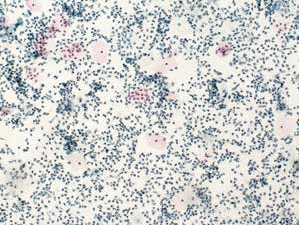

图7-12 不满意样本(低倍、液基、巴氏染色)

炎细胞大量,鳞状上皮细胞少量。鳞状上皮细胞数量不足5 000个,需要重新制片。